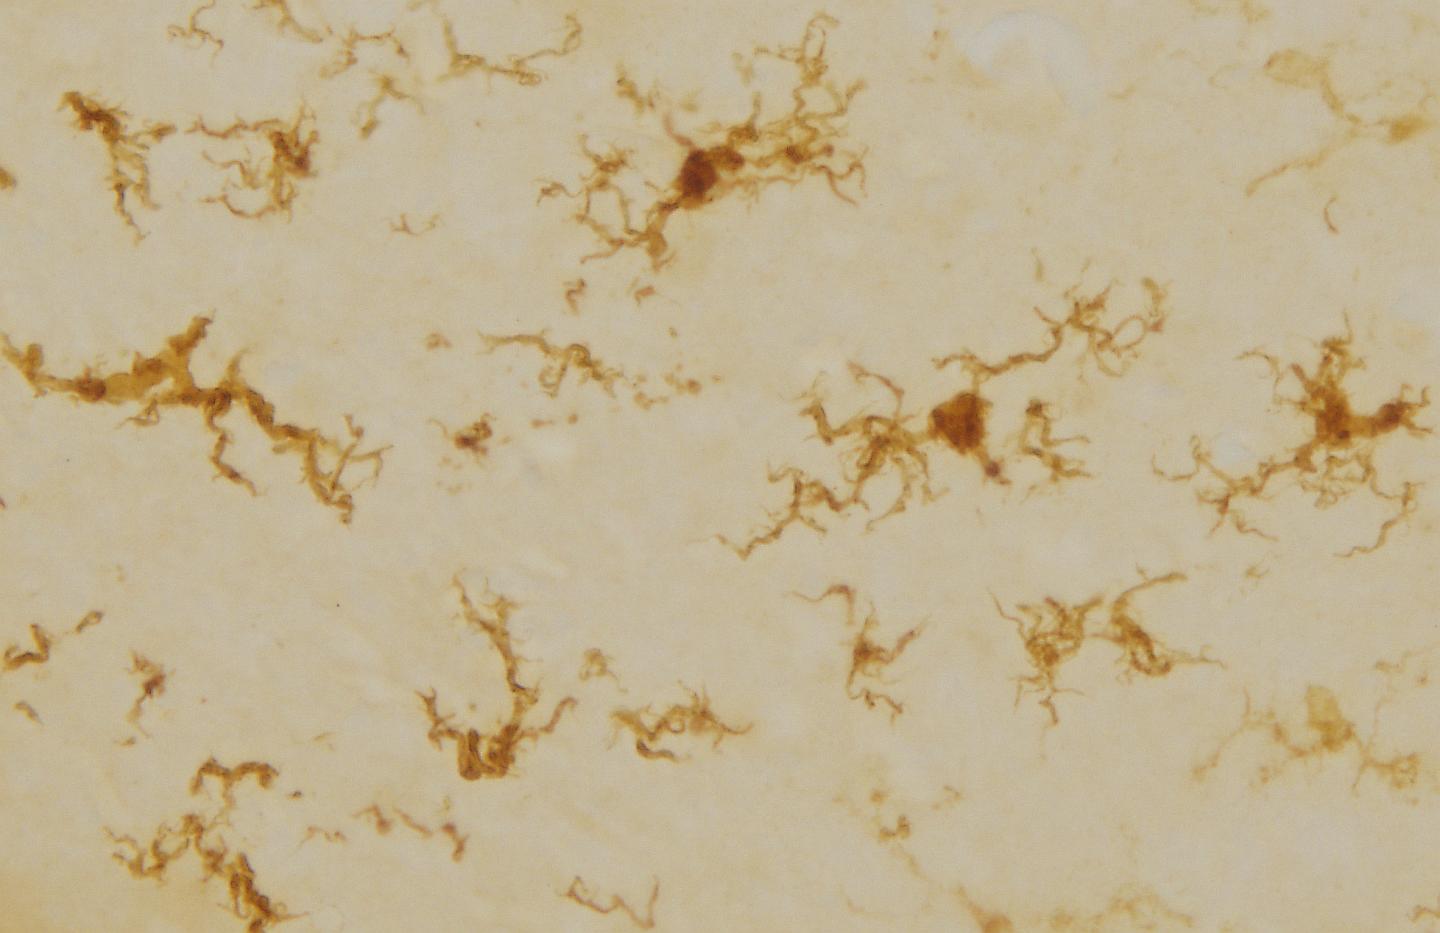

image: A magnified image showing the regenerated microglia. They have a similar shape to the 'activated' shape that the brain's immune cells have when dealing with inflammation.

Importantly, the regenerated microglia were a different shape - similar to the "activated" shape that these cells have when dealing with inflammation.

"We are still exploring what makes these cells different when they repopulate the brain, but their shape tells us they may be more active than usual, potentially making the neurons more effective to encourage better memory," Spencer, an NHMRC Career Development Fellow at RMIT, said.